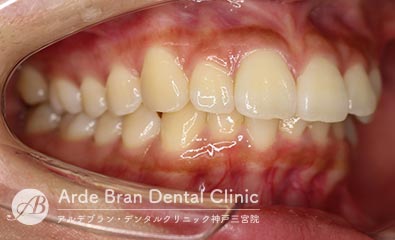

- 叢生/八重歯/歯のがたつき(20代女性 治療期間2年)

- 上下の犬歯の突出と歯のがたつきを主訴に来院されました。特に上下ともに犬歯が大きく前に出ており、噛み合わせに悪影響を及ぼしている状態でした。歯列のスペース不足が顕著であったため、上下左右の第一小臼歯を4本抜歯し、適切な歯列を確保する方針としました。治療では、上下の犬歯を正しい位置へ誘導しながら、全体の噛み合わせを調整。歯列のアーチを整え、前歯のねじれやガタつきも改善しました。治療後は、上下の犬歯が適切な位置に収まり、口元のラインがすっきりと改善。歯並びだけでなく、噛み合わせや清掃性の向上にもつながり、機能的で美しい口元を実現しました。

- 治療前

- 治療後

| 装置名 | インビザライン(マウスピース矯正) |

| 抜歯非抜歯 | 4本抜歯 |

| 治療期間 | 2年 |

| 費用 | インビザラインフル72万円+TAX |